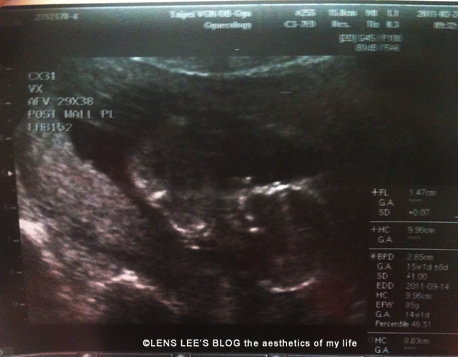

這一次懷孕與上次比較不同的是寶寶的成長好像都比預產期要大幾天,好像真的有比較頭好壯壯一點。

還是很好奇阿閃是什麼性別,超音波掃描技師掃了半天還是搖頭說看不到,她說阿閃現在是“倒立“姿勢,完完全全看不到!腳幾乎都要頂天囉!